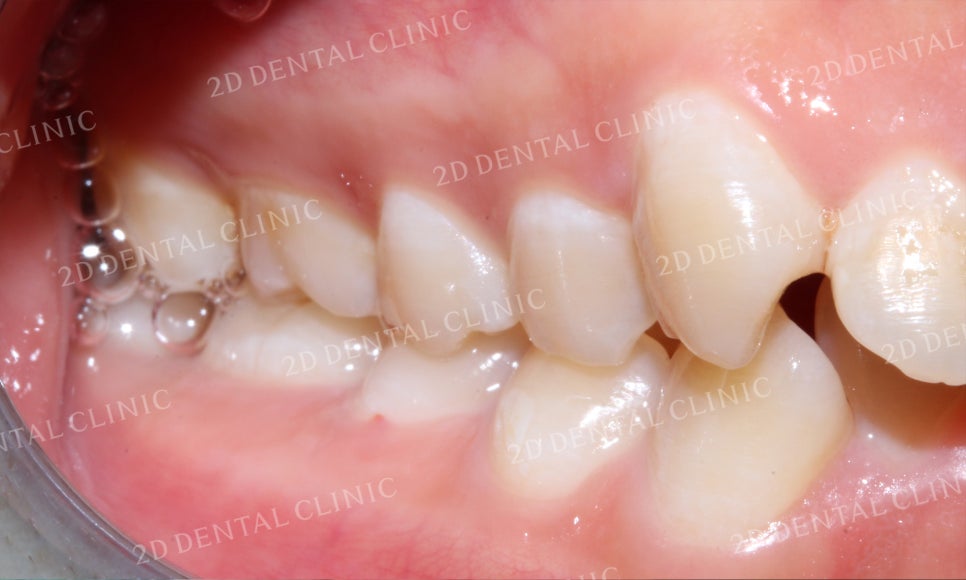

좌측 구치부의 교합 시 모습입니다.

발달한 상악과 미약한 하악의

교합으로 하악이 과도하게

물리는 것을 확인할 수 있습니다.

우측 구치부 역시 좌측과 같은 상태로

상하악 교합이 깊게 물리는 모습입니다.